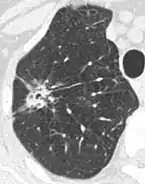

Lung nodule abutting a pulmonary cyst.[9]

• A lung nodule abutting a pulmonary cyst is a rare finding, yet indicating cancer.[9]